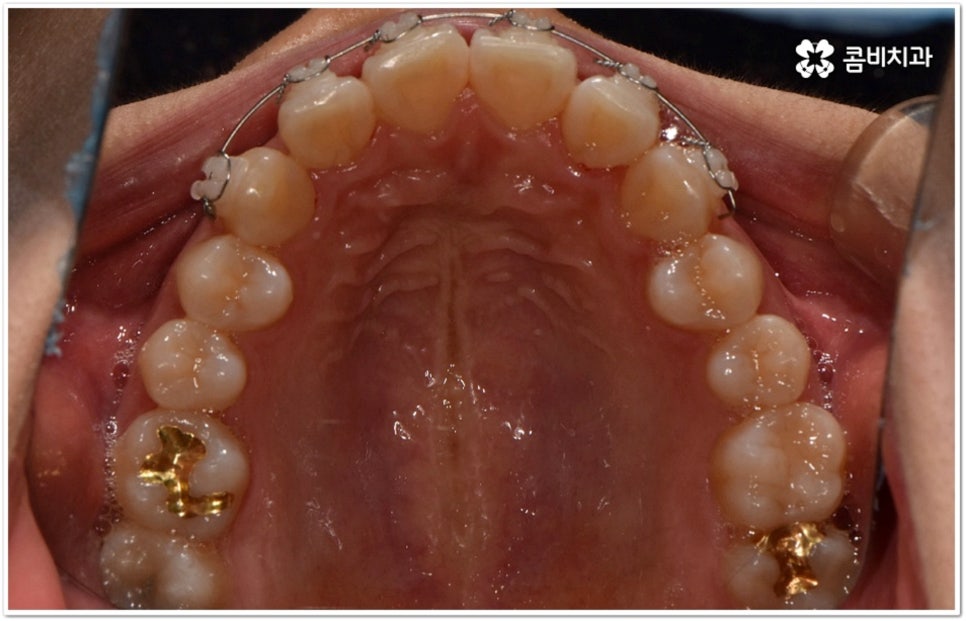

현재는 크게 불편함이 없고 환자분들의 입장에서 볼 때 스스로 교정이 딱히 필요하다고 생각되지 않는다고 해도 정밀 검진을 받아보는 것이 도움이 되는 또 다른 이유는 덧니가 생긴 원인, 구조적인 부분 등을 꼼꼼하게 체크해 봤을 때 혹시라도 추후에 치열이 더 많이 삐뚤어지거나 턱관절에 좋지 않은 영향을 줄 수 있는 상황이라면 미리 대처할 수 있다는 데 있어요. 본을 떠 보고 3D CT 를 이용해 겉으로 보이지 않는 부분까지 함께 살펴보면서 악궁 및 치아의 크기와 각도, 상악과 하악의 발달 정도 등 각자의 상황을 종합적으로 분석해 보면 앞으로의 이동 방향이나 정도 등을 어느 정도 예측해 볼 수 있는데요. 가능하다면 문제가 커진 다음에 바로잡는 것보다 지속적인 관찰을 통해 적절한 시기에 필요한 치료를 하는 것이 시간과 노력을 덜 들이는 방법이 될 거예요.

덧니의 원인에는 여러 가지가 있는데 대표적으로는 유치가 너무 일찍 빠져서 영구치가 제대로 자리를 잡지 못했거나 턱뼈의 크기와 치아 크기가 조화를 이루지 못하는 경우 등 공간이 부족한 상황을 생각해 볼 수 있어요. 덧니는 주로 송곳니가 가장 흔하나, 치열이 공간이 부족할 경우 이론적으로는 어떤 치아라도 덧니가 될 수 있어요. 이때 원인과 정도를 꼼꼼하게 파악하여 만약 해당 부위만 부분 교정이 가능하다면 덧니부분교정 치료를 할 수 있는데요. 덧니부분교정 을 이용하면 원하는 부위에만 브라켓을 부착하여 치아 이동을 시키기 때문에 전체 교정에 비해서 간편하며 치료 기간도 6~8개월 정도로 줄어들고 통증도 많이 감소될 수 있습니다. 비용적인 부담도 덜하며 (삐뚤어진 정도나 상태에 따라 다르겠지만) 보통 덧니부분교정 의 경우 비발치 과정으로 진행되기 때문에 환자분들의 입장에서는 덧니부분교정 을 많이 선호하시는 편이라고 할 수 있어요. 상황에 따라 미니스크류, 치간삭제, 악궁확장장치 등 환자에게 맞는 비발치 방법을 이용하여 도움 받을 수 있습니다.